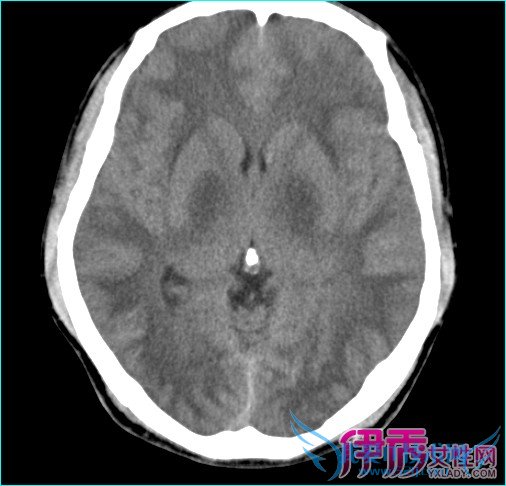

大脑是由上百亿个神经元组成的,而神经元又是由细胞体和神经纤维组成的,细胞体中有细胞核(颜色深),神经纤维中有细胞质(颜色浅)。在大脑中细胞体聚集在大脑表层,看起来颜色深,叫做脑灰质;而神经纤维聚集在大脑内部,看起来颜色浅,叫做脑白质。脑白质病是一种大脑的结构性改变,以中枢神经细胞的髓鞘损害为主要特征,病变累及专门发挥高级大脑功能的白质束。其临床表现从注意力不集中、健忘和个性改变,到痴呆、昏迷甚至死亡。

初步精神状态检查,包括评价注意力不集中的试验、鉴定记忆力障碍的三词延迟回忆试验、评价视觉功能障碍的时钟绘画和评价脑功能的交替运动序列。如果精神状态检查结果可疑,可进一步进行神经精神学测试。如果初步精神状态检查的前两类试验未发现任何缺陷,则可确定无可察觉的大脑损害;如果前两类试验发现异常,可进行大脑神经影像学检查。加权磁共振成像是首选检查手段,是鉴别早期或轻微脑白质病与精神疾病的重要手段,而CT仅能显示重度脑白质损害。